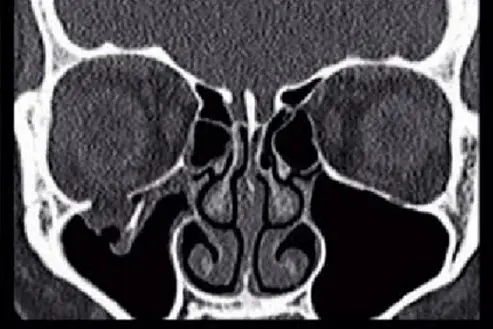

頭頸部 CT的影像如下圖,下列何者為最有可能之診斷?

這是一張頭頸部無顯影劑電腦斷層(Non-contrast CT)的冠狀面(Coronal view)影像。

- 右側眼眶底(影像左側):可以明顯觀察到右側眼眶底(Orbital floor)的骨骼連續性中斷,出現骨折現象。

- 淚滴徵象(Teardrop sign):眼眶內的軟組織(主要為眼眶脂肪 orbital fat 與下直肌 inferior rectus muscle)穿過骨折處,向下突出(herniate)進入右側上頷竇(Maxillary sinus)內,形成一個如水滴般向下垂墜的軟組織陰影,此為典型的「淚滴徵象」。

- 右側上頷竇:除了下墜的眼眶組織外,竇腔內也可見部分混濁與積液(可能為外傷導致的出血或黏膜水腫)。

- 左側眼眶與上頷竇(影像右側):解剖構造完整,眼眶底連續性良好,上頷竇內充滿空氣(呈現黑色低訊號),可作為正常的對照組。

- (A) orbital floor fracture(眼眶底骨折):正確。冠狀面 CT 影像清